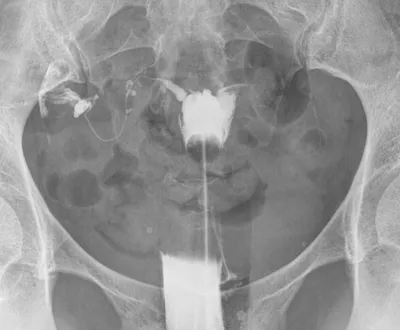

L'hystérosalpingographie est un examen prescrit habituellement dans les cas de stérilité, d'avortements spontanés à répétition, de troubles des règles ou de saignements anormaux.

Il permet à l'aide de l'instillation locale d'un produit de contraste de mieux connaître la forme de l'utérus et de détecter des anomalies : fibromes, polypes ou adhérences.

L'hystérosalpingographie trouve toute son utilité dans l'analyse morphologique et fonctionnelle des trompes : perméabilité, rétrécissement, obstructions, séquelles d'infections.